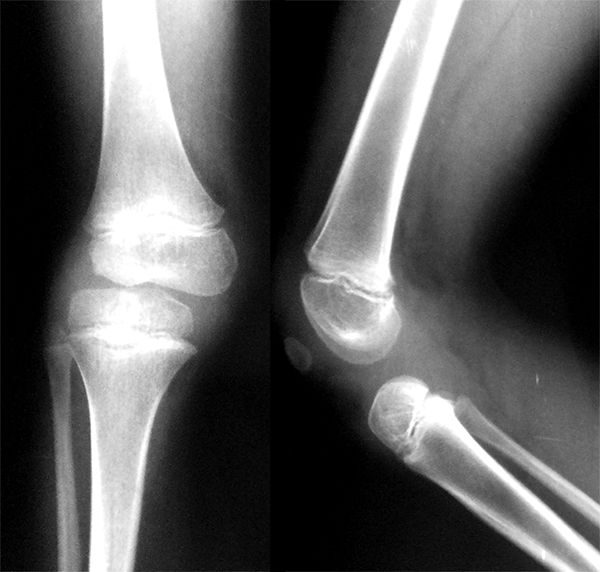

A los seis años consultó por una luxación recurrente habitual de rodilla derecha, luxando la tibia hacia anterior en relación con el fémur al extender la rodilla y con reducción activa de la tibia al flexionarla (video 1).

Los estudios radiológicos confirmaron el diagnóstico clínico (figs. 4 y 5). Se decidió el tratamiento quirúrgico de la luxación femorotibial de su rodilla derecha.

Figura 4: Rx de frente y perfil en la que se puede apreciar la luxación anterior de rodilla.